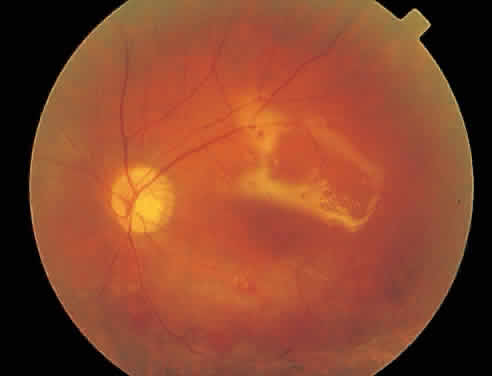

mild anterior uveitis is extremely unusual with AIDS-associated CMV retinitis. The hallmark lesion of CMV retinitis is a necrotizing, full-thickness retinitis that results in retinal cell destruction. CMV often initially affects retinal tissue adjacent to major retinal blood vessels or the optic disc (Fig. 1). This is consistent with the concept that the virus is spread to the retina hematogenously. In most cases, the pattern of infection is classic and distinctive, making clinical diagnosis straightforward. The area of active retinitis has a granular, dirty-white appearance. As the virus attacks the endothelial cells of blood vessels, hemorrhage is common. Advancement in the retinitis by both direct cell-to-cell transmission as well as spread by way of adjacent satellite lesions can be seen. Except for cases in which retinitis is acute, it is common to see areas of healed retinitis beside areas of active necrosis. Areas of burned-out necrosis show absence of any retinal tissue, whereas the underlying retinal pigment epithelium assumes a “salt and pepper” appearance. CMV retinitis can present initially as either large areas of retinal necrosis with hemorrhage or one or more small, focal areas of retinal whitening.1,12,14 These small, focal lesions may on occasion be confused with cotton-wool spots or lesions of toxoplasmosis.5,27 Unlike cotton-wool spots, focal areas of CMV may appear outside the posterior pole. These early, focal infiltrates of CMV may not be associated with retinal hemorrhages or vitreous cells. Over a course that usually spans weeks, infiltrates of CMV tend to assume two different patterns of clinical disease.11,12 The first pattern is called hemorrhagic and is characterized by broad geographic zones of retinal whitening. These large, geographic lesions are usually in close proximity to a major retinal blood vessel or the optic nerve. Satellite lesions are common. When the retinal necrosis associated with CMV retinitis becomes widespread, it is almost invariably associated with retinal hemorrhages. Although the border between necrotic and unaffected retina is sharply demarcated, the border itself appears irregular and jagged. Exudation into the retina or subretinal space may be seen, adding to the granular appearance of the retinitis. Juxtaposition of large zones of white, granular necrosis with those of red retinal hemorrhage has led this appearance of CMV retinitis to be described as either “pizza-pie” or “cheese and ketchup.” The retinal blood vessels, both arteries and veins, in the areas of necrosis commonly appear sheathed, secondary to a vasculitis. As a consequence, secondary retinal vascular occlusions, especially branch retinal vein obstructions, may occur in the course of CMV retinitis. Immune-mediated vascular damage may play a role in the vasculitis.12 Central healing of these lesions will occur as the infection progresses. Avasculitis resembling “frosted branch angiitis” hasbeen reported (Fig. 2).28 A second pattern of CMVretinitis has been labeled “granular” or “brushfireborder.” In this appearance, the focal granular infiltrates enlarge slowly across a line, leaving ever-increasing areas of destroyed retina and atrophic retinal pigment epithelium behind. Hemorrhages and vitreous cells are a less prominent feature. There appears to be direct cell-to-cell transfer of infected virions in this pattern of infection (Figs. 3 and 4). The brushfire border is commonly seen in CMV retinitis lesions anterior to the equator (Fig. 5). The significance, if any, of these two clinical patterns of CMV retinitis is not known, and, in some eyes, both patterns of disease can be seen simultaneously or in sequence. Progression of retinitis has been defined in clinical trials as movement of a lesion border at least 750 μm along a front that is 750 μm or more in length, development of a new CMV lesion in a previously involved eye or in the uninvolved fellow eye of a patient with baseline unilateral disease.29 Without treatment or improvement in the host's immune system, CMV retinitis is a relentless, slowly progressive infection resulting in blindness caused by total retinal necrosis, retinal detachment, or optic nerve involvement, in any combination.